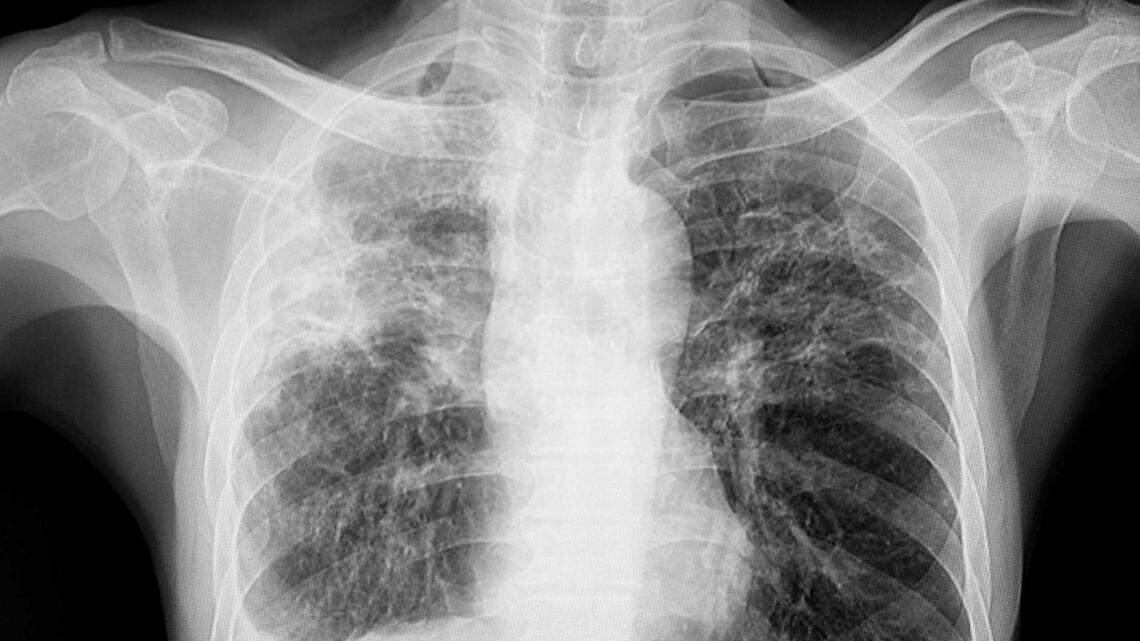

Rogue Tuberculosis Case in Pierce County

A Tacoma woman that the local health department has sought medical compliance from for more than a year for untreated tuberculosis remains at large in the general population.